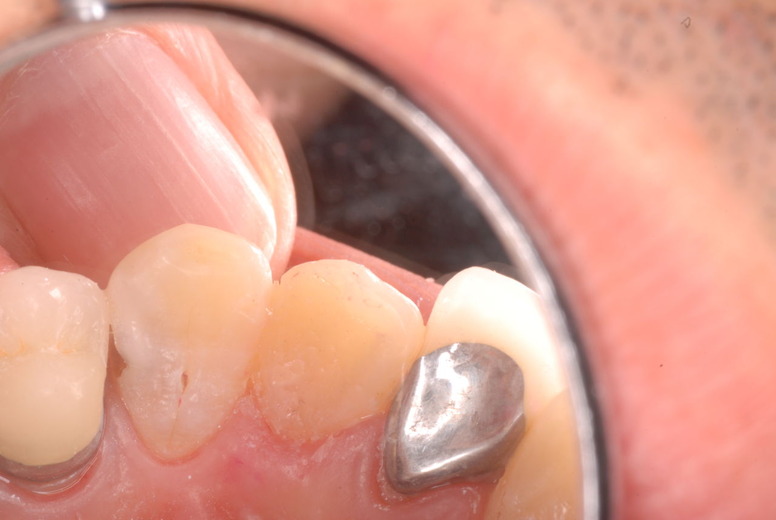

色々不満な入れ歯です。

発音や見える金属が気になるようです。

ご自分でやられても歯茎から血が出ないと話をされていましたが、私がブラシを当てると悲惨な状態であることがわかりました。